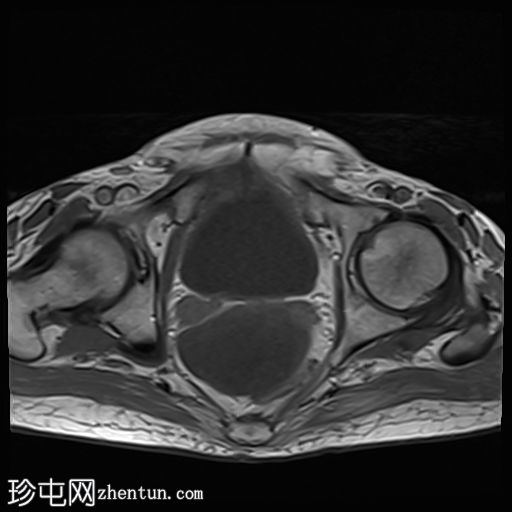

4.jpg

轴向

升结肠壁增厚,尤其前壁,形成肿块,T2信号高,提示其为黏液性肿块。肿块无扩散受限,增强扫描后几乎无强化。

腹腔内可见大量T2信号高、T1信号低至中等的包裹性积液,与腹膜凹陷相符,并导致内脏表面(尤其是肝脏和脾脏)呈扇贝状。这些表现是腹膜假黏液瘤的特征性表现,可能由黏液性肿瘤播散引起。